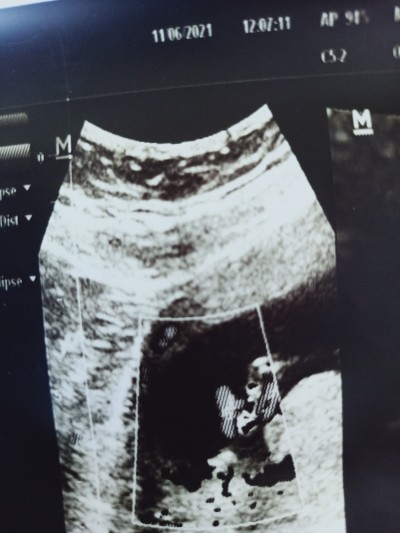

Merhaba cinsiyet erkek denildi ama bu hafta babalar günü bende eşime ve aileme süpriz yapmak istiyorum Dr cinsiyet kisminda fotosunu çekmiş ama hrlde ama geçen hafta  15 bugün 16 oldum yarın tekrar mi gitsem ya da bakar mısınız sizce nedir tecrübeli anneler iyi yorumluyor

Gebelik haftası 16

Pipisi nerde :) evet zaten direk bı anda bakarken erkek bu dedi ben etkendir diye son anda sordum hocam cinsiyeti belli olur mu daha erken ama işte dedim bakım dedi. İnceledi baktı erkek bu dedi bende olayın şoku ciddimisiniz dedim ciddiyim tabi dedi